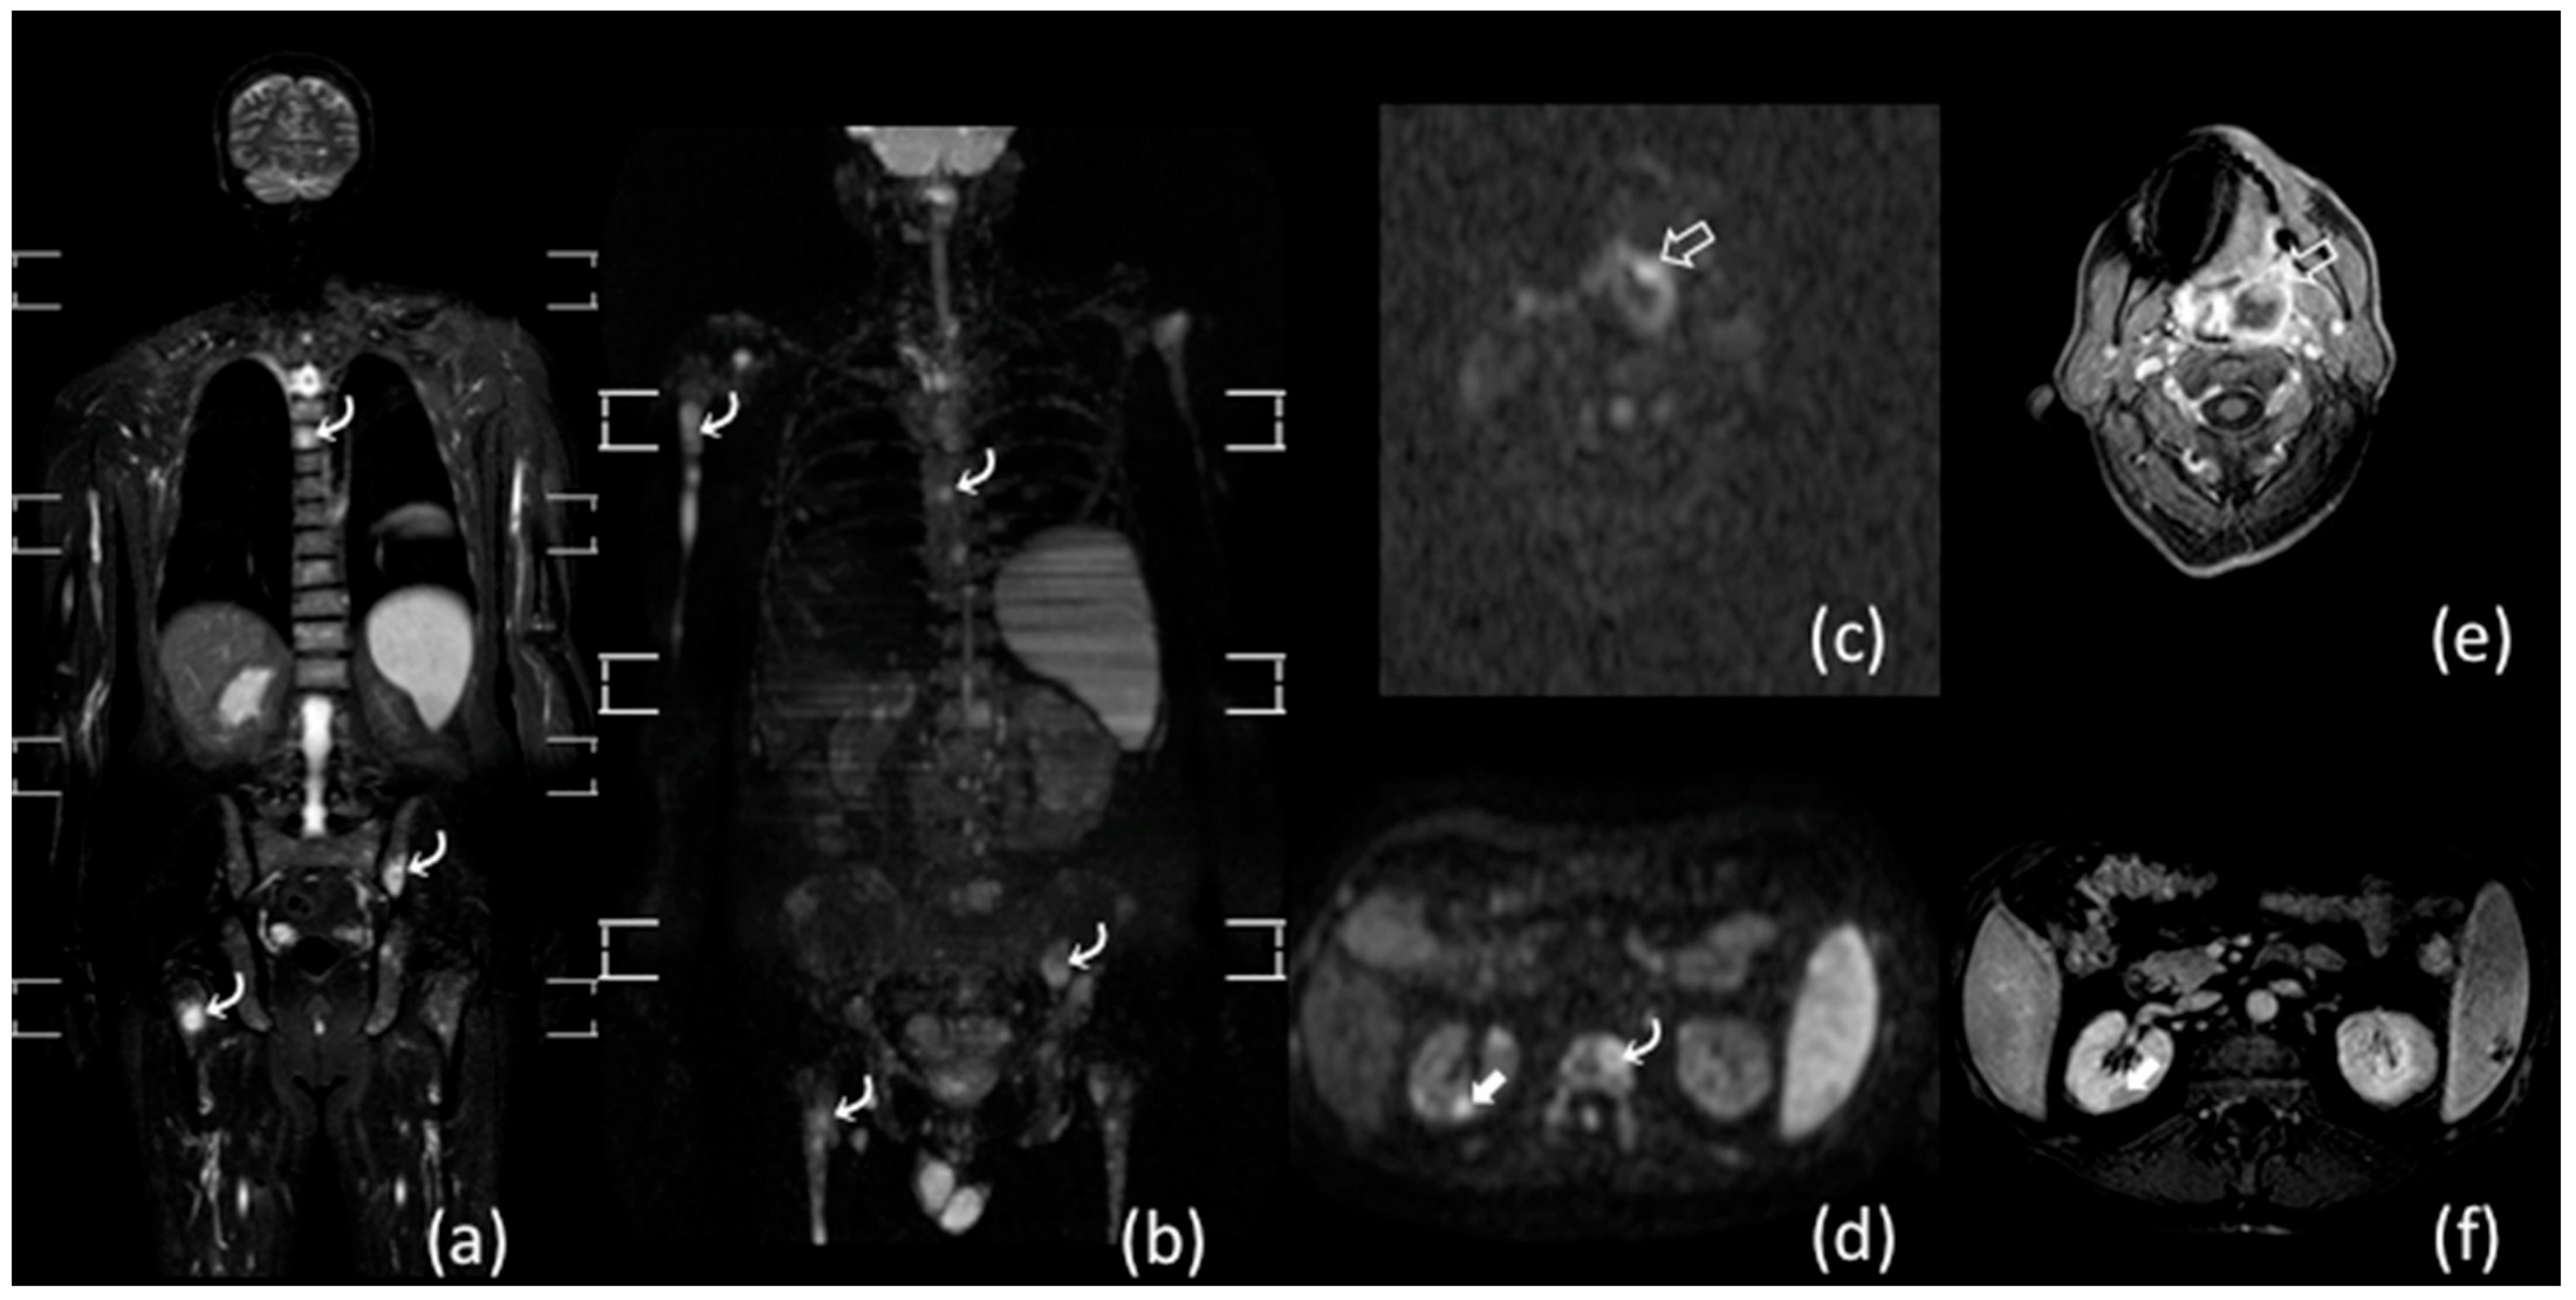

- Albano, D.; Patti, C.; Lagalla, R.; Midiri, M.; Galia, M. Whole-body MRI, FDG-PET/CT, and bone marrow biopsy, for the assessment of bone marrow involvement in patients with newly diagnosed lymphoma. J. Magn. Reson. Imaging 2017, 45, 1082–1089. [Google Scholar] [CrossRef]

- Adams, H.J.A.; Kwee, T.C.; Vermoolen, M.A.; De Keizer, B.; De Klerk, J.M.H.; Adam, J.A.; Fijnheer, R.; Kersten, M.J.; Stoker, J.; Nievelstein, R.A.J. Whole-body MRI for the detection of bone marrow involvement in lymphoma: Prospective study in 116 patients and comparison with FDG-PET. Eur. Radiol. 2013, 23, 2271–2278. [Google Scholar] [CrossRef] [PubMed]

- Haddy, T.B.; Parker, R.I.; Magrath, I.T. Bone marrow involvement in young patients with non-Hodgkin’s lymphoma: The importance of multiple bone marrow samples for accurate staging. Med. Pediatr. Oncol. 2006, 17, 418–423. [Google Scholar] [CrossRef]